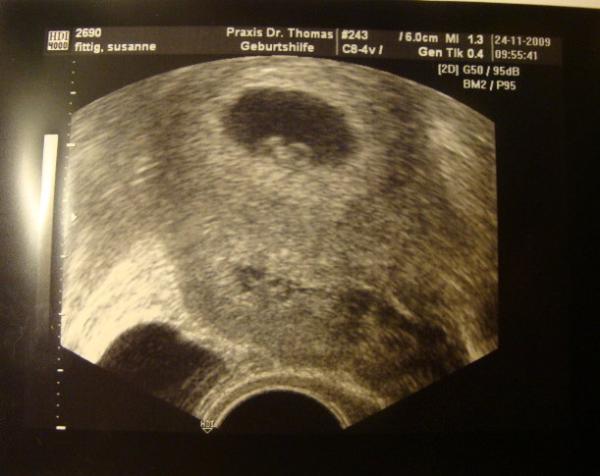

so Mädels heute hab ich wieder langersehnt den termin gehabt alles ok soweit das Herzchen hat geschlagen mir ist echt ein stein vom Herzen gefallen und mein Mann hat Tränchen in den augen gehabt. allerdings wäre ich heute laut Regel 7+4 und laut Us 6+4 aber mein fa hat gesagt wir werden bis zu nächsten untersuchung warten bis man das Baby richtig messen kann . aber ich hab mich gefreut das alles ok ist

hier ein bildchen von heute

Bild zu